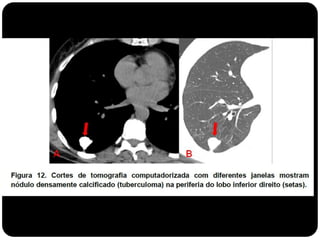

Granuloma de TB

 Calcificação difusa, central ou lamelar  possível considerar

benigno;

 Causa mais comum de NPS: granuloma

(por infecção granulomatosa prévia)